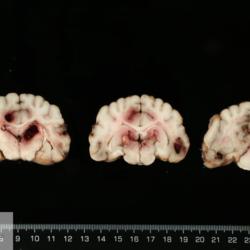

Pàgina anterior de 637 Pàgina següent 3181 total Equine Specie: Equine Organ: Stomach Lesion: Rupture Lesion modifier: - Disease: - Files/Expedient: N-159/16 Not viewed Equine Specie: Equine Organ: Peritoneum Lesion: Peritonitis Lesion modifier: - Disease: - Files/Expedient: N-159/16 Not viewed Canine Specie: Canine Organ: Brain Lesion: Hemorrhage Lesion modifier: - Disease: - Files/Expedient: N-157/16 Position: 252 (1 views) Canine Specie: Canine Organ: Brain Lesion: Vasculitis Lesion modifier: - Disease: - Files/Expedient: N-157/16 Position: 59 (4 views) Feline Specie: Feline Organ: Thymus Lesion: Lymphoma Lesion modifier: - Disease: - Files/Expedient: N-151/16 Position: 87 (3 views) Pàgina anterior de 637 Pàgina següent Títol Select...Avian (Exotic) (110)Avian (Poultry) (76)Bovine (317)Canine (935)Caprine (47)Equine (257)Feline (326)Ferret (19)General (127)Marine mammal (22)Non-human primate (20)Ovine (328)Porcine (379)Rabbit (61)Reptile (38)Rodent (28)Wildlife (91) Format Select...- (60)Abomasum (37)Adrenal gland (10)Blood (7)Blood vessel (50)Body as a whole (19)Bone (57)Bone marrow (21)Brain (93)Cloaca (1)Diaphragm (2)Ear (5)Esophagus (39)Eye (16)Fetus (12)Gallbladder (23)Gizzard (2)Heart (265)Intestine (356)Joint (32)Kidney (443)Larynx (5)Liver (326)Lung (264)Lymph node (91)Mammary gland (10)Mediastinum (1)Muscle (22)Nasal cavity (22)Nerve (7)Omasum (5)Oral cavity (63)Ovary (14)Oviduct (8)Pancreas (7)Parathyroid (5)Penis (10)Peritoneum (65)Pharynx (9)Pituitary gland (6)Placenta (7)Prostate (8)Proventriculus (3)Reticulum (1)Rumen (28)Sinus (7)Skin (181)Spinal cord (15)Spleen (105)Stomach (125)Teeth (1)Testicle (11)Thoracic cavity (31)Thymus (13)Thyroid gland (5)Tongue (32)Tonsils (11)Trachea (11)Urethra (5)Urinay bladder (61)Uterus (27)Vagina (1)Vulva (1)Yolk sac (1) Cobertura Select...- (152)Abomasitis (26)Abscess (27)Acidosis (1)Adenocarcinoma (20)Adenoma (9)Aerosacculitis (6)Agenesis (1)Agnathia (1)Alopecia (7)Amyloidosis (12)Aneurysm (6)Angiectasis (1)Anthracosis (1)Arteritis (11)Arthritis (15)Arthrogryposis (6)Artifact (4)Ascites (13)Atelectasis (8)Atherosclerosis (5)Atresia (1)Atrial septal defect (2)Atrophy (10)Autolysis (7)Bronchitis (6)Bronchopneumonia (26)Cachexia (2)Carcinoma (103)Cardiomyopathy (19)Cellulitis (2)Chemodectoma (4)Cholangiohepatitis (4)Cholangitis (19)Cholecystitis (4)Cholestasis (5)Chondrodysplasia (2)Chondrosarcoma (2)Chronic passive congestion (13)Chylothorax (2)Cirrhosis (6)Coelomitis (3)Coenurus cerebralis (4)Colitis (40)Congestion (17)Conjunctivitis (5)Coronitis (3)Cryptorchidism (3)Cyst (25)Cystitis (24)Dermatitis (69)Diaphragmatic hernia (4)Dilation (28)Discospondylitis (1)Disseminated intravascular coagulation (7)Dyschondroplasia (1)Dysplasia (29)Ectopia cordis (1)Ectopic ureter (1)Edema (55)Emphysema (5)Encephalitis (5)Endocardiosis (14)Endocarditis (26)Endometritis (5)Enteritis (118)Enterolith (6)Epulis (3)Esophagitis (14)Fasciitis (1)Fibrosis (7)Fibrous osteodystrophy (8)Fistula (1)Folliculitis (3)Fracture (2)Gastritis (34)Gingivitis (5)Glioma (8)Glomerulonephritis (21)Glossitis (25)Glycogenosis (1)Gout (8)Granuloma (2)Granulosa cell tumor (4)Hemangioma (9)Hemangiosarcoma (46)Hematoma (8)Hemoglobinuria (2)Hemopericardium (12)Hemoperitoneum (2)Hemorrhage (100)Hemosiderosis (7)Hemothorax (2)Hepatitis (78)Hernia (11)Histiocytosis (3)Hydatid cyst (11)Hydrocephalus (9)Hydrometra (1)Hydronephrosis (22)Hydropericardium (6)Hydrothorax (3)Hydroureter (5)Hyperkeratosis (8)Hyperostosis (4)Hyperplasia (37)Hypertrophy (9)Hypopigmentation (1)Hypoplasia (7)Hypopyon (1)Impaction (6)Infarction (63)Insulinoma (6)Intussusception (5)Jaundice (17)Laminitis (2)Laryngitis (2)Leiomyoma (5)Leukemia (13)Lipidosis (36)Lipoma (7)Lymphadenitis (45)Lymphadenopathy (7)Lymphangiectasia (6)Lymphangitis (5)Lymphoma (221)Malacia (11)Malignant melanoma (15)Mast cell tumor (11)Mastitis (8)Megaesophagus (2)Melanosis (3)Melena (4)Meningioma (6)Meningitis (6)Meningocele (2)Meningoencephalitis (5)Mesothelioma (5)Methemoglobinemia (2)Mineralization (10)Mucocele (5)Mucometra (1)Multilobular bone tumor (1)Mummification (3)Myelofibrosis (1)Myocarditis (4)Myositis (5)Necrosis (81)Nephritis (113)Nephroblastoma (6)Nephrosclerosis (1)Nephrosis (14)Neuritis (1)Obstruction (13)Omasitis (4)Omphalitis (1)Omphalophlebitis (7)Orchitis (4)Osteoarthrosis (5)Osteomyelitis (9)Otitis (2)Palatoschisis (3)Pancreatitis (3)Panniculitis (3)Papilloma (7)Parakeratosis (14)Patent ductus arteriosus (6)Peliosis hepatis (1)Perforation (17)Pericarditis (35)Peritonitis (39)Persistent right aortic arch (1)Pharyngitis (2)Pheochromocytoma (2)Phlebitis (2)Placentitis (6)Pleuritis (21)Pleuropneumonia (24)Pneumonia (109)Pneumothorax (3)Polycystosis (14)Polyp (5)Polyserositis (6)Posthitis (1)Proctitis (4)Prolapse (3)Prostatitis (3)Proventriculitis (1)Pyelonephritis (24)Pyometra (6)Pyothorax (4)Rhinitis (11)Rumenitis (6)Rupture (24)Salpingitis (3)Sarcoma (57)Sclerosis (1)Scoliosis (2)Seminoma (2)Sequestrum (2)Serous atrophy (14)Sinusitis (7)Splenitis (14)Splenomegaly (9)Spondylitis (6)Spondylosis (1)Stenosis (9)Stomatitis (32)Tenosynovitis (2)Teratoma (3)Thricobezoar (2)Thrombosis (16)Tonsilitis (4)Torsion (13)Tracheitis (4)Tympany (7)Typhlitis (8)Typhlocolitis (4)Ulcer (43)Urethritis (1)Urolithiasis (36)Uroperitoneum (1)Uveitis (1)Vasculitis (15)Ventricular septal defect (3)Volvulus (11) Matèria Select... - (14)- (1653)- (152)Abomasitis - Catarrhal (2)Abomasitis - Catarrhal-hemorrhagic (1)Abomasitis - Chronic (1)Abomasitis - Fibrinous-necrotizing (2)Abomasitis - Hyperplasic (5)Abomasitis - Hyperplasic - Chronic (1)Abomasitis - Necrotic (1)Abomasitis - Necrotizing (2)Abomasitis - Ulcerative (5)Adenocarcinoma (9)Aerosacculitis - Granulomatous (1)Amyloidosis - Chronic (1)Arteritis - Necrotic (2)Arteritis - Necrotizing (1)Arthritis - Chronic (4)Arthritis - Fibrinous-purulent (3)Arthritis - Serous (4)Arthritis - Subacute (1)Ascites - Serous (1)Atrophy - Serous (1)Bronchitis - Catarrhal (3)Bronchitis - Suppurative (1)Bronchopneumonia - Catarrhal-purulent (17)Bronchopneumonia - Fibrinous (1)Bronchopneumonia - Granulomatous (1)Bronchopneumonia - Purulent (1)Bronchopneumonia - Suppurative (5)Carcinoma - Adenocarcinoma (33)Carcinoma - Adenocarcinoma - Hepatocellular (2)Carcinoma - Adenocarcinoma - Mucinous (1)Carcinoma - Basosquamous (1)Carcinoma - Cholangiocellular (3)Carcinoma - Hepatocellular (4)Carcinoma - Metastatic (3)Carcinoma - Squamous cell carcinoma (13)Carcinoma - Transitional cell (2)Cardiomyopathy - Dilated (13)Cardiomyopathy - Hypertrophic (6)Cellulitis - Necrotizing (1)Cholangitis - Chronic (8)Cholangitis - Hyperplasic (3)Cholecystitis - Fibrinous-necrotizing (1)Coelomitis - Fibrinous (1)Coelomitis - Granulomatous (1)Colitis - Catarrhal (3)Colitis - Catarrhal-hemorrhagic (1)Colitis - Fibrinous (1)Colitis - Fibrinous-necrotizing (1)Colitis - Fibrinous-necrotizing (Diphtheritic) (6)Colitis - Granulomatous (2)Colitis - Hemorrhagic (4)Colitis - Hemorrhagic-necrotizing (3)Colitis - Necrotizing (2)Colitis - Ulcerative (6)Congestion - Chronic (2)Conjunctivitis - Hyperplasic (1)Conjunctivitis - Purulent (3)Coronitis - Ulcerative (1)Cystitis - Chronic (3)Cystitis - Fibrinous (1)Cystitis - Fibrinous-necrotizing (1)Cystitis - Follicular (1)Cystitis - Hemorrhagic (6)Cystitis - Hemorrhagic-ulcerative (1)Cystitis - Necrotizing (9)Cystitis - Perforated (1)Dermatitis - Granulomatous (14)Dermatitis - Hyperkeratotic (10)Dermatitis - Hyperplasic (proliferative) (1)Dermatitis - Hyperplastic (10)Dermatitis - Necrotizing (4)Dermatitis - Pustular (4)Dermatitis - Ulcerative (2)Dilation - Chronic (1)Discospondylitis - Necrotizing (1)Dysplasia - Follicular (5)Edema - Interstitial (6)Emphysema - Interstitial (1)Encephalitis - Granulomatous (1)Encephalitis - Nonsuppurative (1)Endocardiosis - Mitral (7)Endocardiosis - Mitral - Chronic (5)Endocarditis - Valvular (6)Endocarditis - Valvular - Mitral (7)Endocarditis - Valvular - Pulmonic (1)Endocarditis - Valvular - Subacute (1)Endocarditis - Valvular - Subaortic (5)Endocarditis - Valvular - Tricuspid (4)Endometritis - Purulent (3)Endometritis - Purulent-hemorrhagic (2)Enteritis - Catarrhal (23)Enteritis - Catarrhal - Acute (1)Enteritis - Catarrhal-hemorrhagic (5)Enteritis - Catarrhal-hemorrhagic - Acute (2)Enteritis - Fibrinous (16)Enteritis - Fibrinous - Acute (3)Enteritis - Fibrinous-necrotizing (7)Enteritis - Granulomatous (14)Enteritis - Granulomatous - Chronic (1)Enteritis - Granulomatous - Multifocal (1)Enteritis - Hemorrhagic (17)Enteritis - Hemorrhagic - Acute (1)Enteritis - Hemorrhagic-necrotizing (1)Enteritis - Hyperplasic (proliferative) (4)Enteritis - Necrotizing (4)Enteritis - Necrotizing - Acute (1)Enteritis - Necrotizing - Hemorrhagic (1)Enteritis - Necrotizing-ulcerative (2)Enteritis - Ulcerative (1)Enteritis - Ulcerative-hemorrhagic (1)Esophagitis - Erosive-ulcerative (6)Esophagitis - Necrotizing (4)Esophagitis - Ulcerative (1)Esophagitis - Ulcerative-necrotizing (1)Fasciitis - Fibrinous-purulent (1)Folliculitis - Purulent (2)Gastritis - Catarrhal (2)Gastritis - Chronic (1)Gastritis - Follicular (1)Gastritis - Hemorrhagic (2)Gastritis - Hemorrhagic-necrotizing (1)Gastritis - Hypertrophic (2)Gastritis - Inclusion bodies (1)Gastritis - Mineralization (1)Gastritis - Mycotic (1)Gastritis - Necrotizing (2)Gastritis - Ulcerative (6)Gastritis - Uremic (3)Gingivitis - Erosive (2)Gingivitis - Hyperplasic (proliferative) (1)Gingivitis - Necrotizing (1)Glomerulonephritis - Chronic (7)Glomerulonephritis - Membranoproliferative (3)Glomerulonephritis - Membranoproliferative - Chronic (1)Glomerulonephritis - Membranous (3)Glomerulonephritis - Membranous - Chronic (1)Glomerulonephritis - Proliferative (2)Glomerulonephritis - Subacute (1)Glossitis - Erosive (2)Glossitis - Granulomatous (6)Glossitis - Hyperplasic (1)Glossitis - Hyperplasic (proliferative) (2)Glossitis - Hyperplastic (1)Glossitis - Necrotizing (2)Glossitis - Necrotizing - Focal (1)Glossitis - Ulcerative (6)Glossitis - Ulcerative - Multifocal (1)Glossitis - Ulcerative - Subacute (1)Glycogenosis (1)Granuloma - Eosinophilic (1)Hemangiosarcoma - Metastatic (2)Hemorrhage - Acute (1)Hemorrhage - Subcapsular (3)Hepatitis - Abscess (9)Hepatitis - Acute (3)Hepatitis - Chronic (4)Hepatitis - Chronic interstitial (6)Hepatitis - Granulomatous (7)Hepatitis - Interstitial - Multifocal (1)Hepatitis - Interstitial - Subacute (1)Hepatitis - Necrotizing (17)Hepatitis - Necrotizing - Acute (2)Hepatitis - Necrotizing - Hemorrhagic (1)Hepatitis - Necrotizing - Subacute (1)Hepatitis - Pyogranulomatous (7)Hepatitis - Subacute (4)Hydronephrosis - Chronic (1)Hydropericardium - Chronic (1)Hyperplasia - Erythroid (1)Hyperplasia - Lymphoid (3)Hyperplasia - Myeloid (1)Hyperplasia - Nodular (8)Hypertrophy - Concentric (2)Hypertrophy - Eccentric (3)Infarction - Acute (17)Infarction - Acute - Multifocal (2)Infarction - Chronic (5)Infarction - Chronic - Multifocal (1)Infarction - Subacute (18)Infarction - Subacute - Focal (2)Laminitis - Chronic (2)Laryngitis - Necrotic (1)Laryngitis - Necrotizing (1)Leukemia - Lymphoid leukemia (2)Leukemia - Non-lymphoid leukemia (6)Lipidosis - Multifocal (1)Lipidosis - Panlobular (1)Lipidosis - Panlobular - Generalized (2)Lymphadenitis - Granulomatous (24)Lymphadenitis - Granulomatous - Chronic (3)Lymphadenitis - Hemorrhagic (1)Lymphadenitis - Necrotizing (5)Lymphadenitis - Necrotizing (caseous) (11)Lymphangitis - Granulomatous (1)Lymphangitis - Purulent (1)Lymphangitis - Ulcerative (1)Lymphoma - Alimentary lymphoma (7)Lymphoma - Cutaneous lymphoma (6)Lymphoma - Lymphosarcoma (2)Lymphoma - Mediastinal lymphoma (1)Lymphoma - Multicentric lymphoma (29)Malignant melanoma - Malignant (1)Malignant melanoma - Metastatic (1)Mast cell tumor - Metastatic (1)Mastitis - Fibrinous-purulent (2)Mastitis - Necrotic (1)Mastitis - Purulent (3)Mastitis - Suppurative (1)Meningitis - Fibrinous-purulent (2)Meningitis - Purulent (4)Meningoencephalitis - Necrotizing (3)Meningoencephalitis - Nonsuppurative (2)Mineralization - Metastatic (4)Myocarditis - Fibrous - Chronic (1)Myocarditis - Granulomatous (1)Myositis - Purulent (2)Necrosis - Acute (1)Necrosis - Cortical (5)Necrosis - Follicular (1)Necrosis - Papillary (8)Necrosis - Papillary - Acute (3)Necrosis - Subacute (3)Necrosis - Tubular (6)Nephritis - Embolic (2)Nephritis - Embolic suppurative (7)Nephritis - Granulomatous (27)Nephritis - Granulomatous - Chronic (1)Nephritis - Granulomatous - Multifocal (1)Nephritis - Interstitial (6)Nephritis - Interstitial - Acute (4)Nephritis - Interstitial - Chronic (41)Nephritis - Interstitial - Subacute (12)Nephritis - Purulent (7)Nephritis - Purulent - Acute (2)Nephritis - Purulent - Multifocal (3)Nephrosis - Cholemic (3)Nephrosis - Hemoglobinuric (10)Omasitis - Fibrinous-necrotizing (1)Omasitis - Hyperkeratotic (1)Omasitis - Necrotizing (2)Omphalophlebitis - Fibrinous-purulent (2)Omphalophlebitis - Purulent (3)Orchitis - Necrotizing (1)Osteomyelitis - Necrotizing (7)Osteomyelitis - Purulent (2)Otitis - Necrotizing (1)Otitis - Proliferative (1)Pancreatitis - Acute (1)Pancreatitis - Chronic (1)Pancreatitis - Granulomatous (1)Panniculitis - Fibrinous-purulent (1)Panniculitis - Necrotic (1)Panniculitis - Parasitic (1)Perforation - Acute (2)Pericarditis - Fibrinous (19)Pericarditis - Fibrinous - Subacute (1)Pericarditis - Fibrinous-necrotizing (1)Pericarditis - Fibrinous-purulent (3)Pericarditis - Fibrous (1)Pericarditis - Fibrous - Chronic (1)Pericarditis - Gangrenous (6)Pericarditis - Granulomatous (1)Pericarditis - Granulomatous - Chronic (2)Peritonitis - Acute (1)Peritonitis - Fibrinous (11)Peritonitis - Fibrinous - Subacute (1)Peritonitis - Fibrinous-purulent (5)Peritonitis - Fibrous (3)Peritonitis - Granulomatous (6)Peritonitis - Purulent (1)Peritonitis - Purulent-hemorrhagic (1)Peritonitis - Pyogranulomatous (3)Pharyngitis - Fibrinous-necrotizing (1)Pharyngitis - Ulcerative (1)Pheochromocytoma - Metastatic (1)Phlebitis - Purulent (1)Placentitis - Fibrinous-necrotizing (1)Placentitis - Necrotic (1)Placentitis - Necrotizing (1)Pleuritis - Chronic (1)Pleuritis - Fibrinous (3)Pleuritis - Fibrinous-purulent (2)Pleuritis - Fibrous (2)Pleuritis - Granulomatous (3)Pleuritis - Hyperplastic (2)Pleuritis - Purulent (2)Pleuritis - Pyogranulomatous (1)Pleuropneumonia - Fibrinous (13)Pleuropneumonia - Fibrinous-necrotizing (5)Pleuropneumonia - Granulomatous (2)Pleuropneumonia - Hemorrhagic-necrotizing (4)Pneumonia - Aspiration (11)Pneumonia - Bronchointerstitial (4)Pneumonia - Bronchointerstitial - Subacute (1)Pneumonia - Embolic (5)Pneumonia - Granulomatous (37)Pneumonia - Granulomatous - Multifocal (4)Pneumonia - Hemorrhagic-necrotizing (2)Pneumonia - Interstitial (7)Pneumonia - Interstitial - Acute (8)Pneumonia - Interstitial - Chronic (6)Pneumonia - Interstitial - Subacute (15)Pneumonia - Necrotizing (2)Pneumonia - Pyogranulomatous (2)Pneumonia - Verminous (5)Polyserositis - Fibrinous (6)Polyserositis - Fibrous (1)Proctitis - Fibrinous-necrotizing (1)Proctitis - Parasitic (2)Prostatitis - Purulent (1)Pyelonephritis - Acute (2)Pyelonephritis - Chronic (3)Rhinitis - Catarrhal (2)Rhinitis - Fibrinous (1)Rhinitis - Granulomatous (4)Rhinitis - Purulent (3)Rumenitis - Acute (1)Rumenitis - Erosive (1)Rumenitis - Necrotizing (1)Rupture - Acute (3)Sarcoma - Fibrosarcoma (12)Sarcoma - Hemangiosarcoma (11)Sarcoma - Histiocytic (7)Sarcoma - Metastatic (1)Sarcoma - Multilobular tumor of bone (1)Sequestrum - Chronic (2)Sinusitis - Suppurative (1)Splenitis - Granulomatous (8)Splenitis - Granulomatous - Chronic (1)Splenitis - Necrotizing (3)Splenitis - Necrotizing (caseous) (2)Spondylitis - Necrotizing (2)Stenosis - Intestinal (1)Stenosis - Valvular - Subaortic (4)Stomatitis - Erosive (12)Stomatitis - Erosive-ulcerative (3)Stomatitis - Fibrinous-necrotizing (1)Stomatitis - Fibrinous-necrotizing (Diphtheritic) (1)Stomatitis - Granulomatous (1)Stomatitis - Hyperplasic (1)Stomatitis - Hyperplasic (proliferative) (1)Stomatitis - Necrotizing (2)Stomatitis - Ulcerative (5)Stomatitis - Ulcerative - Multifocal (1)Stomatitis - Ulcerative-necrotizing (1)Tonsilitis - Necrotizing (4)Torsion - Acute passive hyperemia (5)Tracheitis - Catarrhal (3)Tracheitis - Fibrinous (1)Tracheitis - Granulomatous (1)Typhlitis - Catarrhal (1)Typhlitis - Fibrinous-necrotizing (2)Typhlitis - Hemorrhagic (2)Typhlitis - Ulcerative-hemorrhagic (1)Typhlocolitis - Fibrinous-necrotizing (2)Typhlocolitis - Proliferative (1)Ulcer - Chronic (6)Ulcer - Multifocal (2)Ulcer - Mycotic (1)Ulcer - Perforated (6)Urethritis - Hemorrhagic (1)Urolithiasis - Chronic (2)Uveitis - Granulomatous (1)Vasculitis - Granulomatous (1)Vasculitis - Necrotizing (1) Editor Select...- (1970)Acidosis (2)Actinobacillosis (Pleuropneumonia) (11)Aelurostrongylosis (2)African horse sickness (13)African swine fever (14)Alopecia X (1)Anaplasmosis (4)Anthrax (2)Aortic thromboembolism (feline) (7)Ascariasis (15)Aspergillosis (18)Atopic dermatitis (1)Atrophic rhinitis (3)Babesiosis (6)Blackhead (1)Bluetongue (11)Border disease (2)Bovine viral diarrhea (21)Brucellosis (2)Candidiasis (5)Canine distemper (14)Caprine arthritis-encephalitis (2)Capture myopathy (1)Cardiac insufficiency (17)Caseous lymphadenitis (7)Chlamydiosis (2)Classical swine fever (19)Clostridiosis (19)Coccidiosis (9)Coenurosis (4)Colibacillosis (21)Contagious ecthyma (7)Copper toxicosis (11)Cowdriosis (Heartwater) (3)Cryptococcosis (3)Cryptosporidiosis (2)Cysticercosis (23)Demodicosis (1)Diabetes (1)Dicrocoeliosis (5)Dictyocaulosis (4)Dirofilariasis (7)Discoid lupus erythematosus (3)Echinococcosis (17)Edema disease (7)Egg drop syndrome (1)Encephalitozoonosis (5)Enterotoxemia (1)Enzootic bovine leukosis (46)Epitheliogenesis imperfecta (3)Equine rhinopneumonitis (2)Equine verminous arteritis (strongylosis) (7)Erysipelas (5)Exudative epidermitis (7)Fasciolasis (11)Feline eosinophilic dermatoses (1)Feline hepatic lipidosis (8)Feline histiocytosis (4)Feline infectious peritonitis (38)Feline leukemia (4)Feline lower urinary tract disease (3)Feline panleukopenia (16)Feline viral rhinotracheitis (1)Flea allergy dermatitis (1)Foot and mouth disease (2)Gasterophilosis (4)Glasser's disease (15)Gousiekte (4)Gout (6)Haemonchosis (9)Hemolytic anemia (4)Hemorrhagic diathesis (1)Hepatic insufficiency (11)Hepatosis dietetica (7)Herpesvirosis (6)Hyperadrenocorticism (7)Hyperparathyroidism (10)Hypertrophic osteopathy (6)Hypervitaminosis D (1)Hypodermosis (1)Inclusion body hepatitis (4)Infectious bovine rhinotracheitis (5)Infectious bronchitis (5)Infectious canine hepatitis (13)Influenza (4)Juvenile nephropathy (8)Lamb dysentery (4)Leishmaniasis (28)Leptospirosis (1)Leukosis (5)Listeriosis (4)Lumpy skin disease (3)Maedi-visna (4)Malignant catarrhal fever (12)Mange (6)Mannheimiosis (5)Marek's disease (7)Metabolic bone disease (2)Mucoid enteropathy (5)Mulberry heart disease (5)Myasis (1)Mycobacteriosis (22)Mycosis fungoides (6)Myxomatosis (3)Necrobacillosis (5)Neonatal isoerythrolysis (6)Nocardiosis (4)Oestrosis (2)Onchocerciasis (1)Osteochondrosis (1)Ostertagiosis (6)Ovine pulmonary adenocarcinoma (5)Oxyuriasis (1)Pacheco's disease (4)Papillomatosis (6)Paratuberculosis (18)Parvovirosis (17)Pasteurellosis (11)Pemphigus foliaceus (1)Periodontal disease (1)Polioencephalomalacia of ruminants (4)Polyarteritis nodosa (3)Polycystic kidney disease (13)Porcine circovirosis (11)Porcine dermatitis and nephropathy syndrome (9)Porcine proliferative enteropathy (4)Porcine reproductive and respiratory syndrome (6)Porcine stress syndrome (1)Pox (13)Pregnancy toxemia (3)Proventricular dilatation disease (2)Pseudotuberculosis (yersiniosis) (2)Psittacine beak and feather disease (PBFD) (5)Pyoderma (4)Q fever (4)Rabbit hemorrhagic disease (2)Renal insufficiency (12)Reticuloendotheliosis (2)Rhodococcosis (1)Rickets (1)Rinderpest (2)Salmonellosis (34)Sarcosporidiosis (2)Schmallenberg (7)Septicemia (23)Spirocercosis (11)Streptococcosis (5)Strongylosis (1)Swine dysentery (5)Systemic coronavirosis (5)Tetralogy of Fallot (5)Theileriosis (13)Thromboembolism (5)Toxoplasmosis (11)Transmissible viral proventriculitis (1)Traumatic reticuloperitonitis (3)Traumatism (16)Tuberculosis (58)Ulcerative lymphangitis (1)Uremic syndrome (20)Viral arthritis (6)White muscle disease (9)Wobbler syndrome (2)Xanthomatosis (1)Zygomycosis (4) Idioma Select...- (1180)Bacterial (501)Degeneration (106)Fungal (46)Hemodynamic (112)Idiopathic (22)Inflammation (58)Malformation (88)Neoplasia (343)Nutritional (41)Parasitic (243)Physical/Chemical (93)Toxic (44)Viral (304) Ítem destacat Porcine Sow. Porcine Ulcerative Dermatitis Syndrome (PUDS). Interface dermatitis. Lesions were neither painful nor pruritic. University of Pretoria, South…